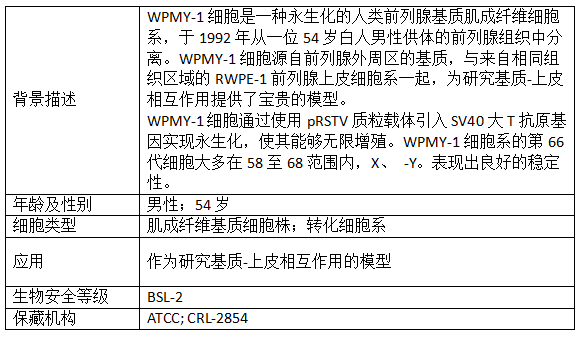

【1】Webber MM, Trakul N, Thraves PS, Bello-DeOcampo D, Chu WW, Storto PD, Huard TK, Rhim JS, Williams DE. A human prostatic stromal myofibroblast cell line WPMY-1: a model for stromal-epithelial interactions in prostatic neoplasia. Carcinogenesis. 1999 Jul;20(7):1185-92. doi: 10.1093/carcin/20.7.1185. PMID: 10383888.

【2】Heitzer MD, DeFranco DB. Hic-5/ARA55, a LIM domain-containing nuclear receptor coactivator expressed in prostate stromal cells. Cancer Res. 2006 Jul 15;66(14):7326-33. doi: 10.1158/0008-5472.CAN-05-2379. PMID: 16849583.

【3】Heitzer MD, DeFranco DB. Hic-5/ARA55: a prostate stroma-specific AR coactivator. Steroids. 2007 Feb;72(2):218-20. doi: 10.1016/j.steroids.2006.11.010. Epub 2006 Dec 12. PMID: 17166536.